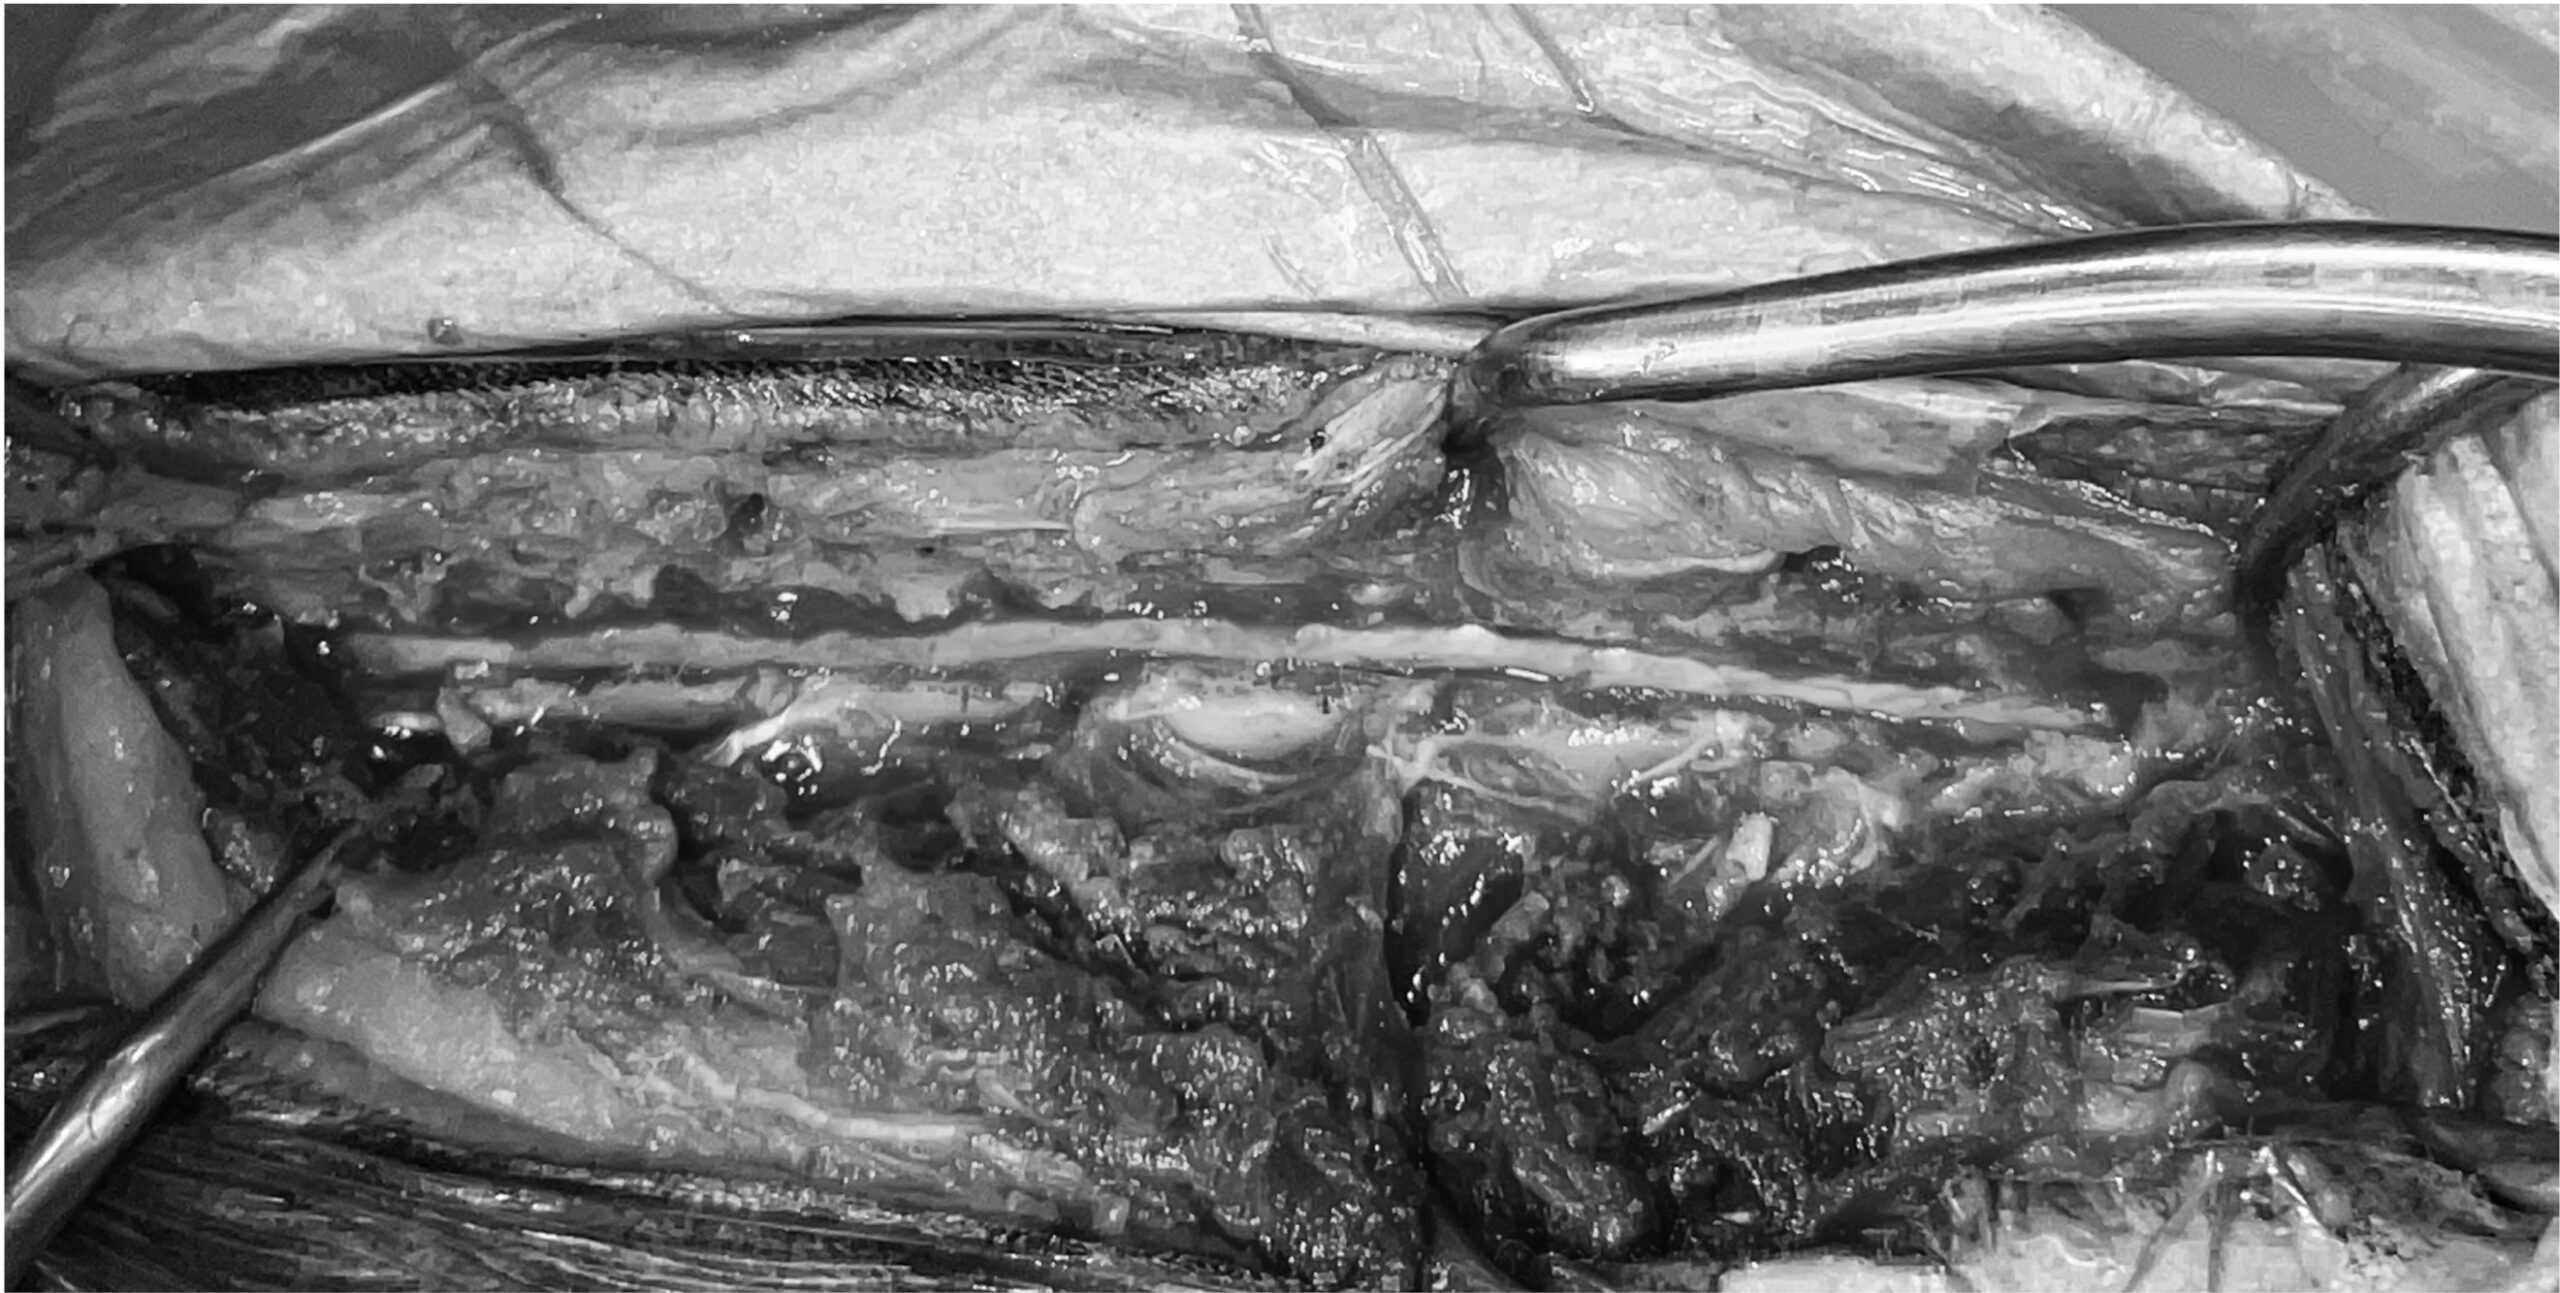

術中写真

広範囲片側椎弓切除 硬膜切開術を実施